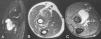

La radiografía mostraba una masa de partes blandas en la fosa antecubital, sin signos evidentes de osteoartritis del codo. En la ecografía se evidenció una masa de ecoestructura mixta, con zonas de contenido líquido anecoico y otras áreas hiperecógenas en las que se sospechaba la presencia de grasa (fig. 1). Se practicó una resonancia magnética (RM) (General Electric, 1.5T) con una antena de superficie de extremidad y se realizaron secuencias sagital fast spin-echo (FSE) T2 supresión grasa y axiales FSE T1, FSE T2 supresión grasa y FSE T1 supresión grasa tras la administración de contraste (gadolinio quelado a dietilenotriamino pentaacético [Gd-DTPA]). Se identificó una masa circunscrita que se extendía a lo largo de la bursa bicipitorradial del codo y rodeaba el tendón del bíceps, con una señal heterogénea a expensas de un componente de tipo fluido correspondiente a derrame en la bursa y focos de tejido graso como pequeñas formaciones polipoides desde la pared hacia el interior de la tumoración. Tras la administración de contraste se evidenció un realce importante de la pared de la masa y de sus proliferaciones (fig. 2).

Ecografía. Imagen longitudinal en la fosa antecubital del codo. Masa de ecoestructura mixta, con un contenido líquido anecoico y zonas hiperecoicas que parten desde su pared en forma de vellosidades (*). La lesión se encuentra en la ubicación característica de la bursa bicipitorradial, por encima de la inserción del tendón braquial anterior (ba).